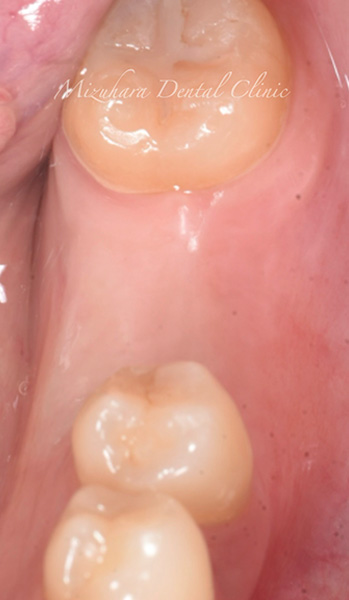

CASE

症例紹介

三鷹の歯医者【みずはら歯科・矯正歯科 三鷹】